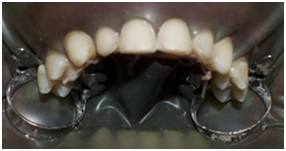

No dental decay was detected. Neither was bone/root resorption. From a periodontal perspective, the patient has quite satisfactory gingival health. He has a stable posterior occlusion after the orthodontic treatment (Figure 1). Whenever esthetic procedures are considered, emphasis must be put on gingival health. Thus, brushing technique had to be optimized. Periodontal treatment, including scaling and root planning should be first realized.

Figure 1 Preoperative view: final step of the orthodontic treatment.